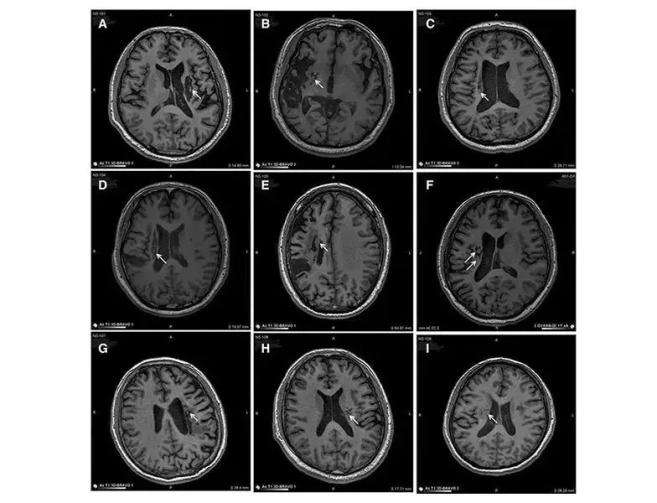

脑卒中会导致神经元损伤。STEM CELL TRANSL MED上的研究表明,干细胞可以再生修复受损的大脑神经元,从而减轻脑卒中患者的后遗症症状:在9名不同年龄的脑卒中偏瘫患者中,应用干细胞移植到脑内梗塞区取得了显著的临床效果。

9例患者的影像学显示病变区域的组织都发生了明显变化影像学显示,移植到脑内梗塞病灶的干细胞通过分化为神经系统的各类细胞,分泌营养因子,促进神经和血管再生,修复受损的血-脑脊液屏障,减轻炎症反应等,促进脑梗死动物的神经功能恢复,使9例临床患者的偏瘫症状得到了显著改善。